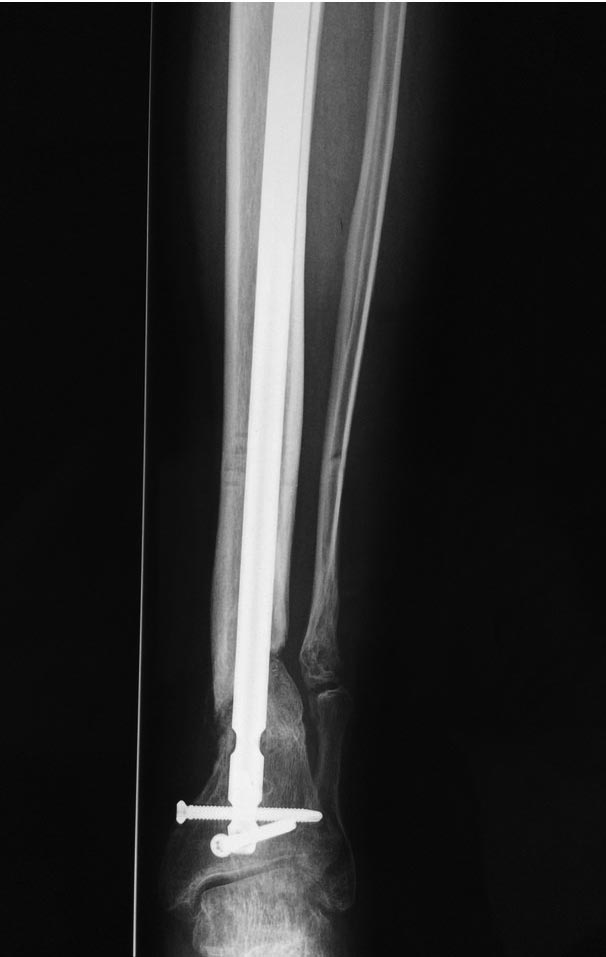

Уважаемые коллеги выразите Ваше мнение по следующему случаю. Молодой

человек, 27 лет, находится на лечении с диагнозом: Ложный сустав

большеберцовой кости в нижней трети, фиксированный интрамедуллярным

блокированным стержнем (12.02.2014 г), ложный сустав малоберцовой кости

в нижней трети левой голени, посттравматический артроз левого

голеностопного сустава 1 стадии. Укорочение левой нижней конечности на

В феврале 2014 г выполнил первым этапом: Фиксацию ложного

сустава в АНФ с восстановлением осей сегментов. Через семь дней БИОС с

рассверливанием.

После операции - вальгус голеностопного сустава. Гладкое течение

послеоперационного периода. Нагрузка по переносимости боли. Через 6

недель динамизация, через 2 недели стали мигрировать 2 фронтальных

винта. Пытался подкрутить, пришлось удалить.